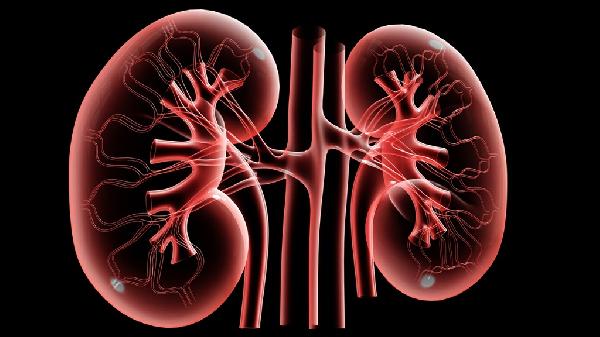

從最初的眼瞼浮腫到後來爬樓梯喘不過氣,身體用各種方式發出紅色預警。直到某天尿液變成醬油色,才被緊急送醫。檢查結果顯示,腎臟功能已經喪失近80%,必須終身透析治療。

碳酸飲料裏的磷酸鹽會與鈣結合形成結晶,這些””小石頭””可能堵塞腎小管。某運動飲料看似補充電解質,實際鈉含量堪比醬油,迫使腎臟加班工作。

膀.胱就像被不斷吹脹的氣球,尿液倒流可能引發腎盂腎炎。那些開會時寧可憋著也不去衛生間的人,腎臟正在默默抗議。

尿液中出現的細密泡沫像啤酒沫一樣久久不散,可能是蛋白質洩漏的跡象。正常人夜間排尿0-1次,如果變成頻繁起夜的””廁所打卡族””就要當心。

2. 難以消退的水腫

即使保證八小時睡眠,仍然像沒充電的手機。腎臟產生的促紅細胞生成素減少時,身體供氧不足就會持續倦怠。